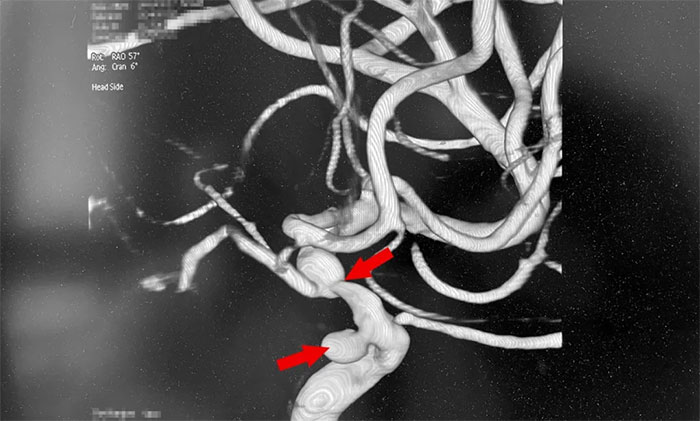

为进一步明确诊断,王大妈接受了全脑血管造影DSA检查,发现左颈内动脉眼动脉段动脉瘤(约3mm)伴左颈内动脉眼动脉段重度狭窄。神经内科4A病区主任席刚明教授、神经内科4A病区副主任王贵平博士会诊指出,左颈内动脉眼动脉段重度狭窄就是王大妈右侧肢体活动不利等症状的“元凶”,如不及时解除血管狭窄,一旦颈内动脉闭塞,就会发生脑梗死!此外,一旦脑动脉瘤破裂,将导致蛛网膜下腔出血!“左颈内动脉眼动脉段重度狭窄”和“左颈内动脉眼动脉段动脉瘤”就像潜伏在患者体内的“不定时炸弹”,随时都有被“引爆”的风险,导致严重致残甚至危及生命。

▲ 脑动脉狭窄合并脑动脉瘤